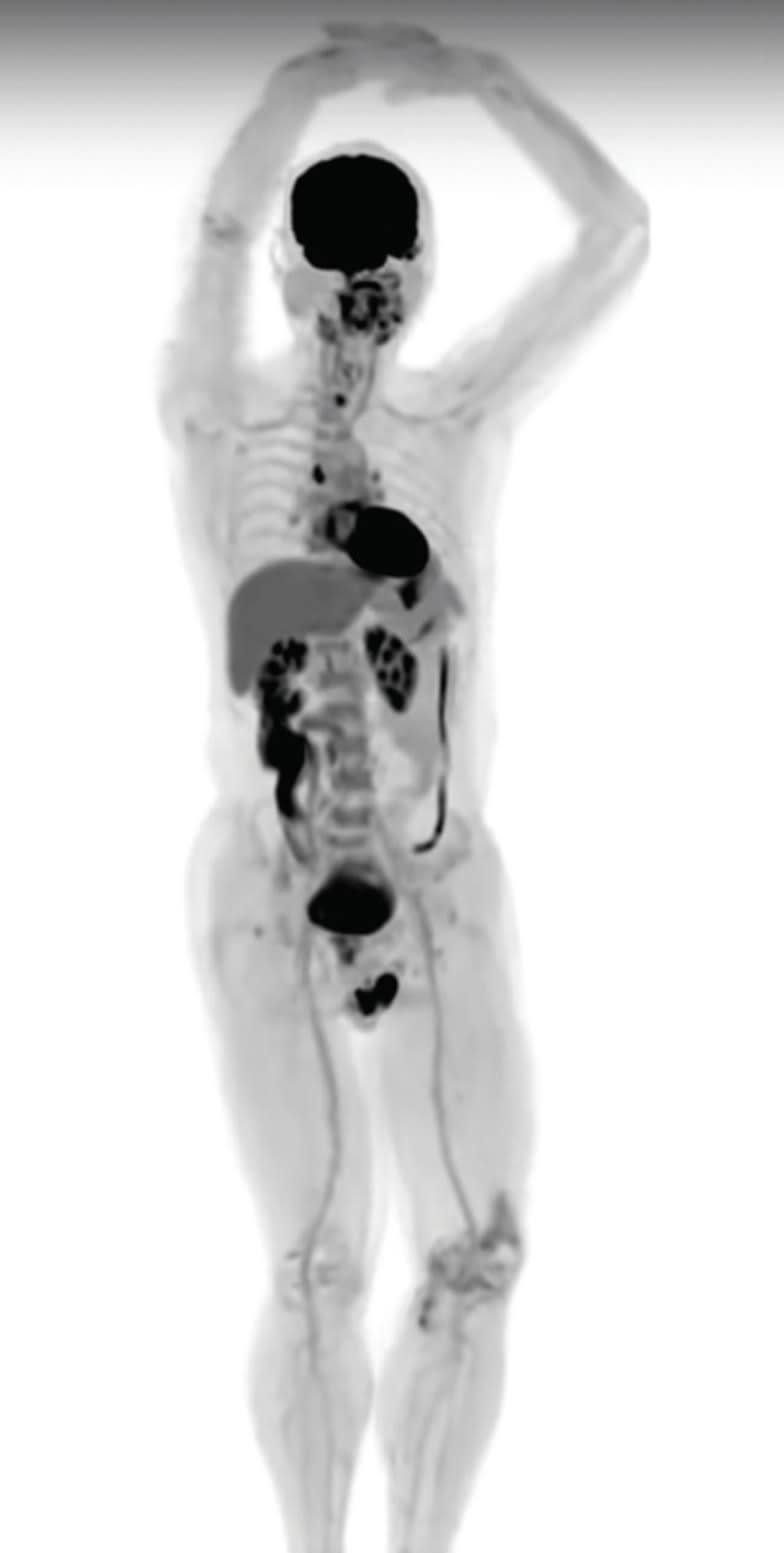

EXPLORER, the world's first medical imaging scanner that can capture a 3D picture of the whole human body at once, has produced its first scans.

The brainchild of UC Davis scientists Simon Cherry and Ramsey Badawi, EXPLORER is a combined positron emission tomography (PET) and x-ray computed tomography (CT) scanner that can image the entire body at the same time. Because the machine captures radiation far more efficiently than other scanners, EXPLORER can produce an image in as little as one second and, over time, produce movies that can track specially tagged drugs as they move around the entire body.

The first images from scans of humans using the new device were shown at the Radiological Society of North America meeting in November in Chicago. The scanner has been developed in partnership with Shanghai-based United Imaging Healthcare (UIH), which built the system based on its latest technology platform and will eventually manufacture the devices for the broader healthcare market.

Badawi, chief of nuclear medicine at UC Davis Health and vice-chair for research in the department of radiology, says he was dumbfounded when he saw the first images, which were acquired in collaboration with UIH and the department of nuclear medicine at the Zhongshan Hospital in Shanghai.

“The level of detail was astonishing, especially once we got the reconstruction method a bit more optimized,” he says. “We could see features that you just don't see on regular PET scans. And the dynamic sequence showing the radiotracer moving around the body in three dimensions over time was, frankly, mind-blowing. There is no other device that can obtain data like this in humans, so this is truly novel.”